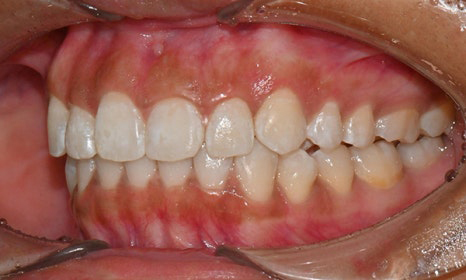

치아 상태는 어땠냐면요:

위아래 앞니 사이에 공간이 벌어져 있었어요.

앞니가 삐뚤빼뚤한 덧니도 있었죠.

윗니와 아랫니가 너무 깊게 맞물리는

과개교합이 있었어요.

왼쪽 아래 작은어금니가 90도 돌아가 있었는데,

이로 인해 왼쪽 치아 배열과 교합이 좋지 않았죠.

개포동교정치과

초진시 구내사진 (2025. 3.31)